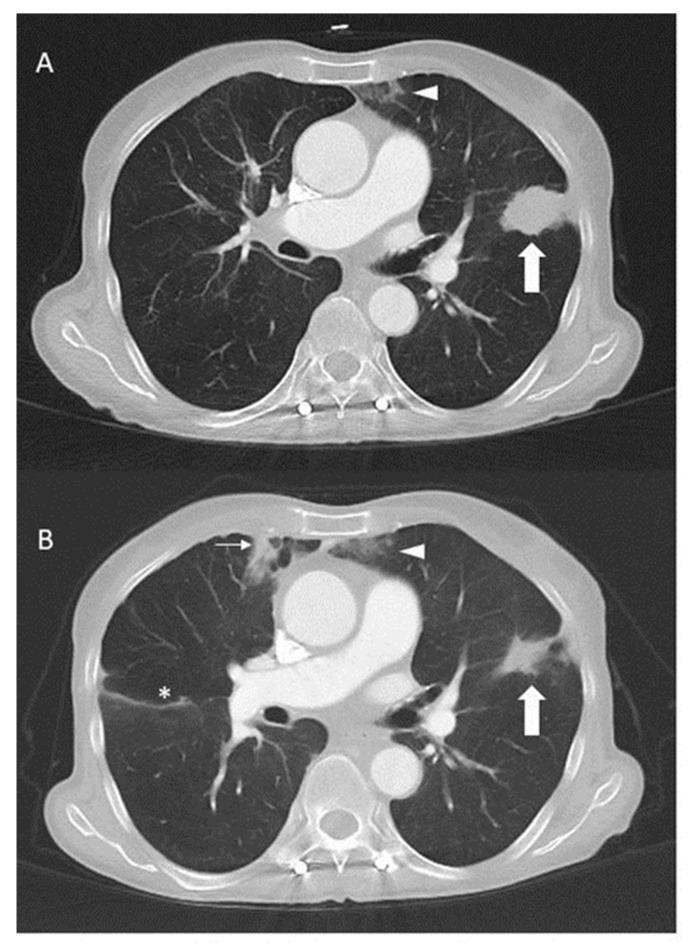

We present the case of a 70-year-old never-smoking female patient with () p.L858R-mutated metastatic non-small cell lung cancer (NSCLC). After three months of first-line treatment with erlotinib, progression occurred and platinum/pemetrexed was initiated, followed by a response for more than two years. After the progression, the molecular testing of a vertebral metastasis revealed a () translocation and a (2) p.S310F mutation, in addition to the known p.L858R mutation. Crizotinib then led to a durable response of 17 months. The molecular retesting of the tumour cells obtained from the recurrent pleural effusion revealed the absence of the translocation, whereas the and mutations were still present. Afatinib was added to the crizotinib, and the combination treatment resulted in another durable response of more than two years. The patient died more than 7 years after the initial diagnosis of metastatic NSCLC. This case demonstrates that the repeated molecular testing of metastatic NSCLC may identify new druggable genomic alterations that can impact the patient management and improve the patient outcome.

我们报告了一例 70 岁从不吸烟的女性转移性非小细胞肺癌(NSCLC)患者,其存在 () p.L858R 突变。一线使用厄洛替尼治疗三个月后出现进展,随后开始使用铂类/培美曲塞治疗,疗效持续超过两年。疾病进展后,对脊柱转移灶进行的分子检测显示存在 () 易位和 (2) p.S310F 突变,此外还存在已知的 p.L858R 突变。克唑替尼治疗后患者获得了长达 17 个月的持久缓解。对复发性胸腔积液中肿瘤细胞进行的分子重新检测显示, 易位缺失,但 和 突变仍然存在。在克唑替尼的基础上加用阿法替尼,联合治疗后患者又获得了超过两年的持久缓解。该患者在诊断为转移性 NSCLC 后超过 7 年死亡。该病例表明,对转移性 NSCLC 的重复分子检测可能会发现新的可用药基因组改变,从而影响患者的管理并改善患者的预后。